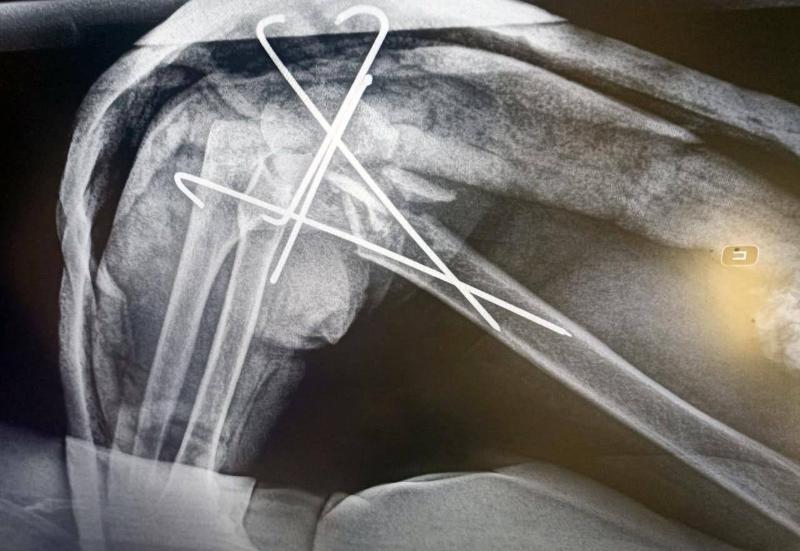

Пожилую пациентку в медучреждение доставила бригада скорой помощи: пенсионерку сбила машина. Специалисты диагностировали у пострадавшей переломы правого плеча, костей левого предплечья и правой большеберцовой кости.

«Перелом плеча был открытым, в связи с чем выполнялась первичная хирургическая обработка раны. После соответствующей подготовки женщина была прооперирована. Врачи одномоментно выполнили четыре операции – остеосинтез мыщелков правого плеча, остеосинтез обеих костей левого предплечья, остеосинтез мыщелков правой большеберцовой кости. Остеосинтез – метод соединения обломков костей металлическими вставками. Операция длилась около двух часов», – рассказал заведующий травмоцентра Долгопрудненской больницы Максим Цымбал.